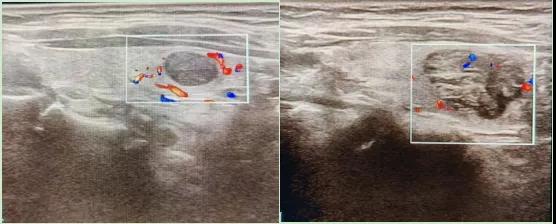

彩色血流顯示:用紅藍(lán)色標(biāo)記血流信號,區(qū)分腫瘤的供血情況。

1.形態(tài):良性多呈圓形,邊界清晰;惡性可能不規(guī)則、邊緣模糊。

2.回聲:低回聲結(jié)節(jié)風(fēng)險較高(像“烏云”一樣暗)。

3.鈣化:細(xì)小砂礫樣鈣化提示惡性可能。

4.血流信號:惡性結(jié)節(jié)常有豐富紊亂的血流。